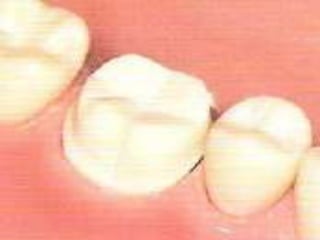

INCRUSTACIONES ONLAY